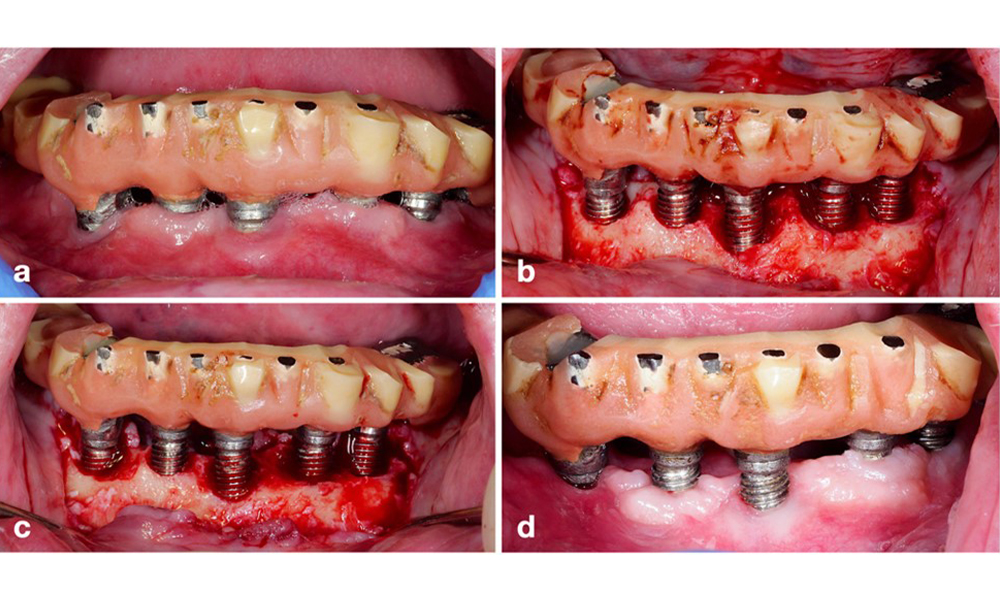

Management of peri-implantitis at implants judged as treatable consists of a non-surgical phase, which is often followed by surgical intervention. For the non-surgical approach, similar measures as those applied for the treatment of peri-implant mucositis are used; based on laboratory experiments air-polishing devices with a subgingival nozzle appear to provide certain advantages in terms of biofilm removal, compared to hand- or ultrasonic instruments (Herrera et al. 2023; Moharrami et al. 2019; Ronay et al. 2017) (figure 9).

Patient case with peri-implantitis. The non-surgical treatment is performed by using the supragingival (a-b) and subgingival handpiece of an air-polishing device (c-d). Removing the supra-construction provides better access to the implant surface (d).

Figure 9. Patient case with peri-implantitis. The non-surgical treatment is performed by using the supragingival (a-b) and subgingival handpiece of an air-polishing device (c-d). Removing the supra-construction provides better access to the implant surface (d).

Yet, the non-surgical approach often has limitations in accessing the implant surface, leading to insufficient decontamination. This is indeed reflected in the clinic, where disease resolution after non-surgical treatment of peri-implantitis is rather unpredictable and recurrence is observed for most cases, i.e., disease resolution was reported to occur only in less than every second case (Ramanauskaite et al. 2021). Therefore, the outcome of non-surgical treatment needs to be evaluated after about 6 weeks, and in cases of moderate or advanced peri-implantitis, surgery should be expected.

The prosthetic restoration should be removed during both non-surgical and surgical treatment to improve access to the implant surface. The choice of surgical intervention (e.g., resective, reconstructive, or combined) depends on several factors: (1) defect morphology (e.g., horizontal, dehiscence, intra-osseous, or combined) (figure 10), (2) implant surface (i.e., turned or modified/”rough”), and (3) presence or absence of sufficient keratinised and attached mucosa.